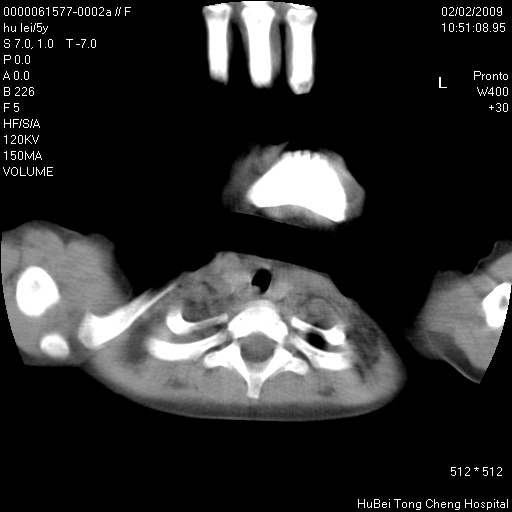

标题: PED1732:M5Y,右肺囊性占位!

患者:男,5。无明显不适,拍胸片考虑右肺囊肿。

行ct扫描,图象如下:

右肺巨大囊肿或包虫

考虑先天性巨大支气管肺囊肿,建议包虫实验除外肺包虫。

右肺巨大囊性占位性病变;考虑巨大肺囊肿,不排除淋巴管瘤可能。

病灶与前胸壁和右上纵隔、叶间裂界限不清,病灶前缘及内侧缘看不到正常的肺组织,不能排除包裹性积液。